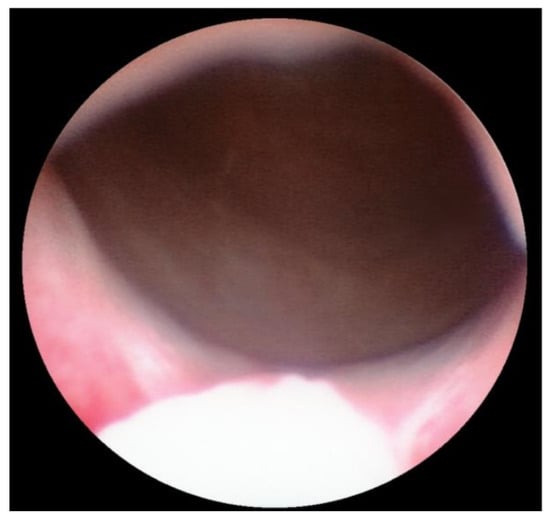

Transurethral cystoscopy displayed a wide open bladder neck at the beginning of the procedure (Figure 5). Under guidance by antegrade suprapubic endoscopy, transurethral retrograde bladder neck injection was performed at the 3 o’clock and 9 o’clock positions (Figure 6). Subsequently, bladder neck injection at the 6 o’clock and 12 o’clock positions was performed through antegrade percutaneous suprapubic endoscopy. Direct antegrade and retrograde visualization confirmed effectiveness of the luminal occlusion (Figure 7). As a (positive) consequence of effective injection, visibility of the optimal location for injection was compromised with increasing volume of the bulking agent. The combined injection technique is helpful to reduce this limitation as much as possible.

Figure 5.

Transurethral cystoscopy: wide open bladder neck.

Retrograde cystoscopy confirming effectiveness of luminal occlusion (before injection: see Figure 5).